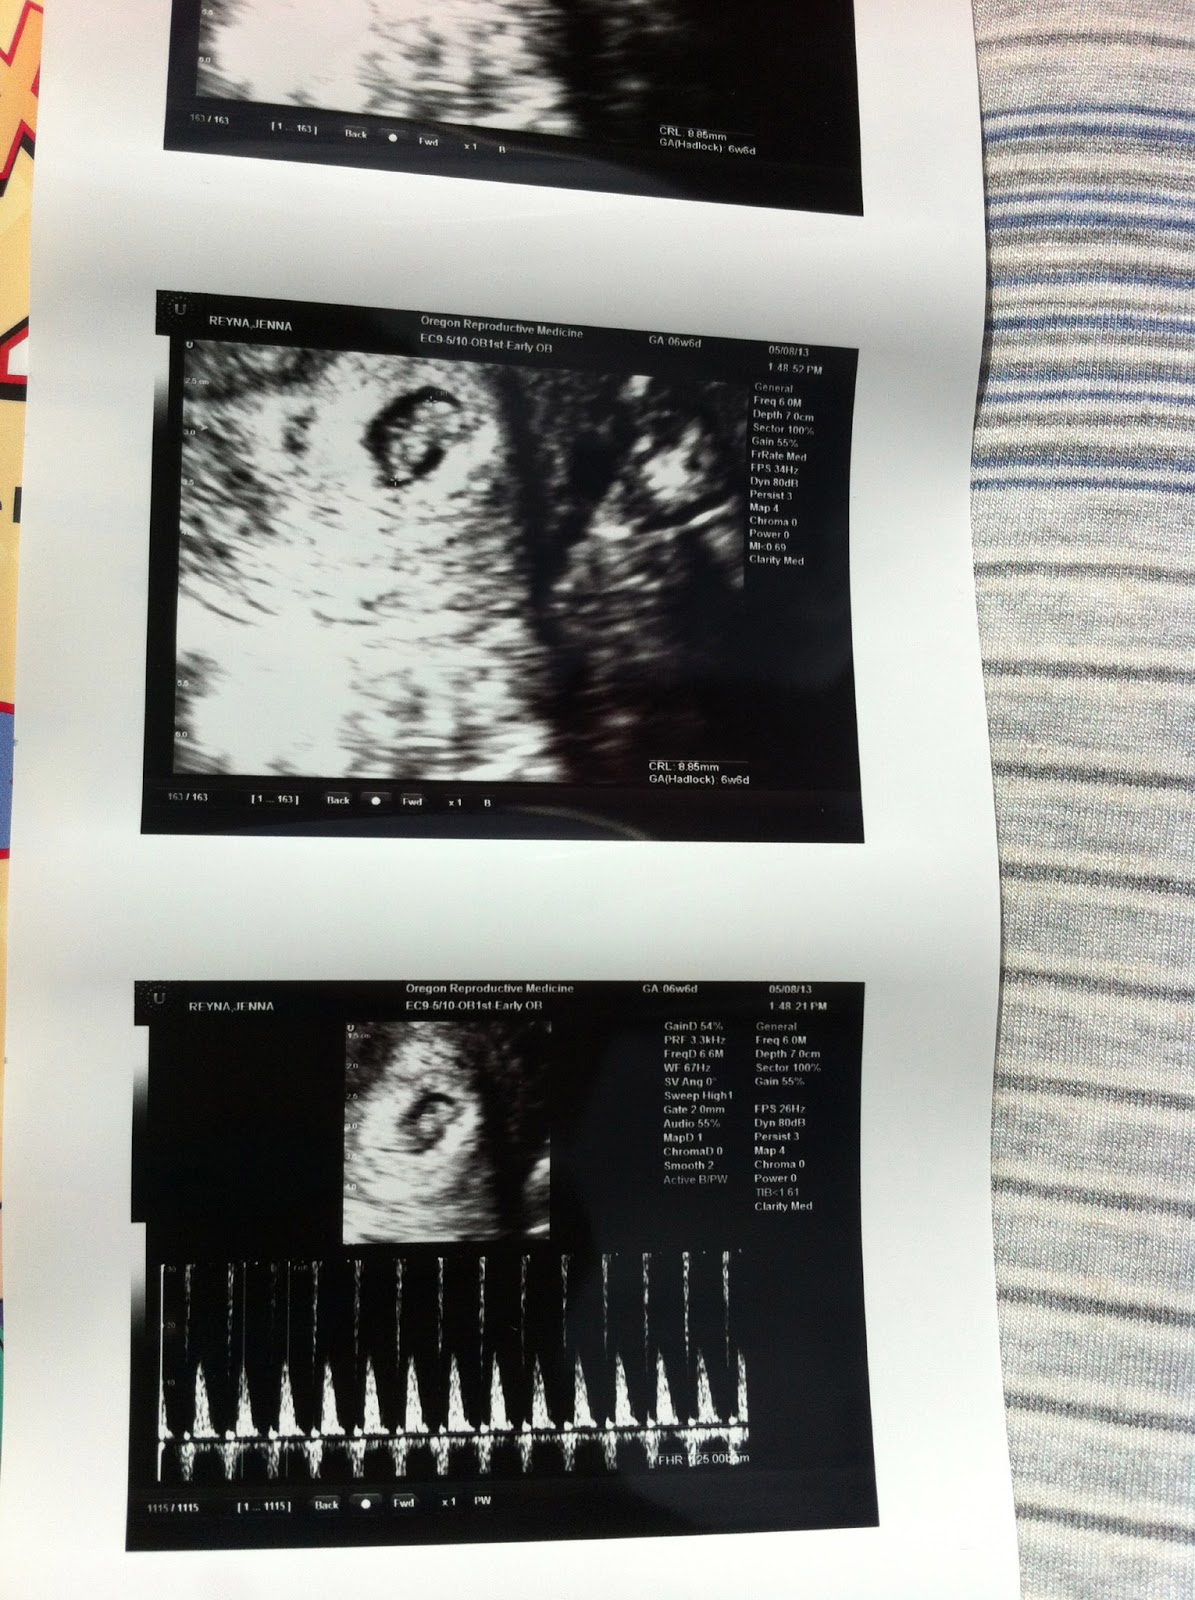

The day before we planned to exclaim our great news more publicly, our hearts broke. The day before my calendar read, "12 week-mark!"... ended in pools of tears. Yes, we were expecting. Our hearts and lives forever changed by our sweet growing baby. All seemed so perfect. Too perfect perhaps. With months of trials and heart ache leading up to getting pregnant (as we had discovered that I have fertility troubles-a topic for another day), our growing little one was such a welcomed addition to our family. Words cannot express how joyous I felt, how grateful we were. It was difficult to contain our excitement. Friends and family celebrated along side us. Little "t-rex" (as my parents nicknamed the babe) was loved. Adored. Cherished. This week was a huge week. Monumental. I would have made it to the "safe zone"- 3 months. All prior ultrasounds and blood work had been perfect, all was looking great. Or so we thought...

After 2 co-workers tried to find heart tones during 2 different weeks without success, I began to worry. I realized that all of my nausea had disappeared. This, I thought was great news. Turns out, it wasn't. With these two puzzle pieces put together, concern set in.

Called my OB in the morning. Went in with Andrew by my side. Confirmed. Tears. Heartbroken. Many tears.

Was sent in for a second confirmatory ultrasound. More tears and new images to replay in my mind.

Per the doctor, we had lost our little baby weeks prior. My body has yet to realize this and respond. Part of me is gone. Part of my heart is missing.